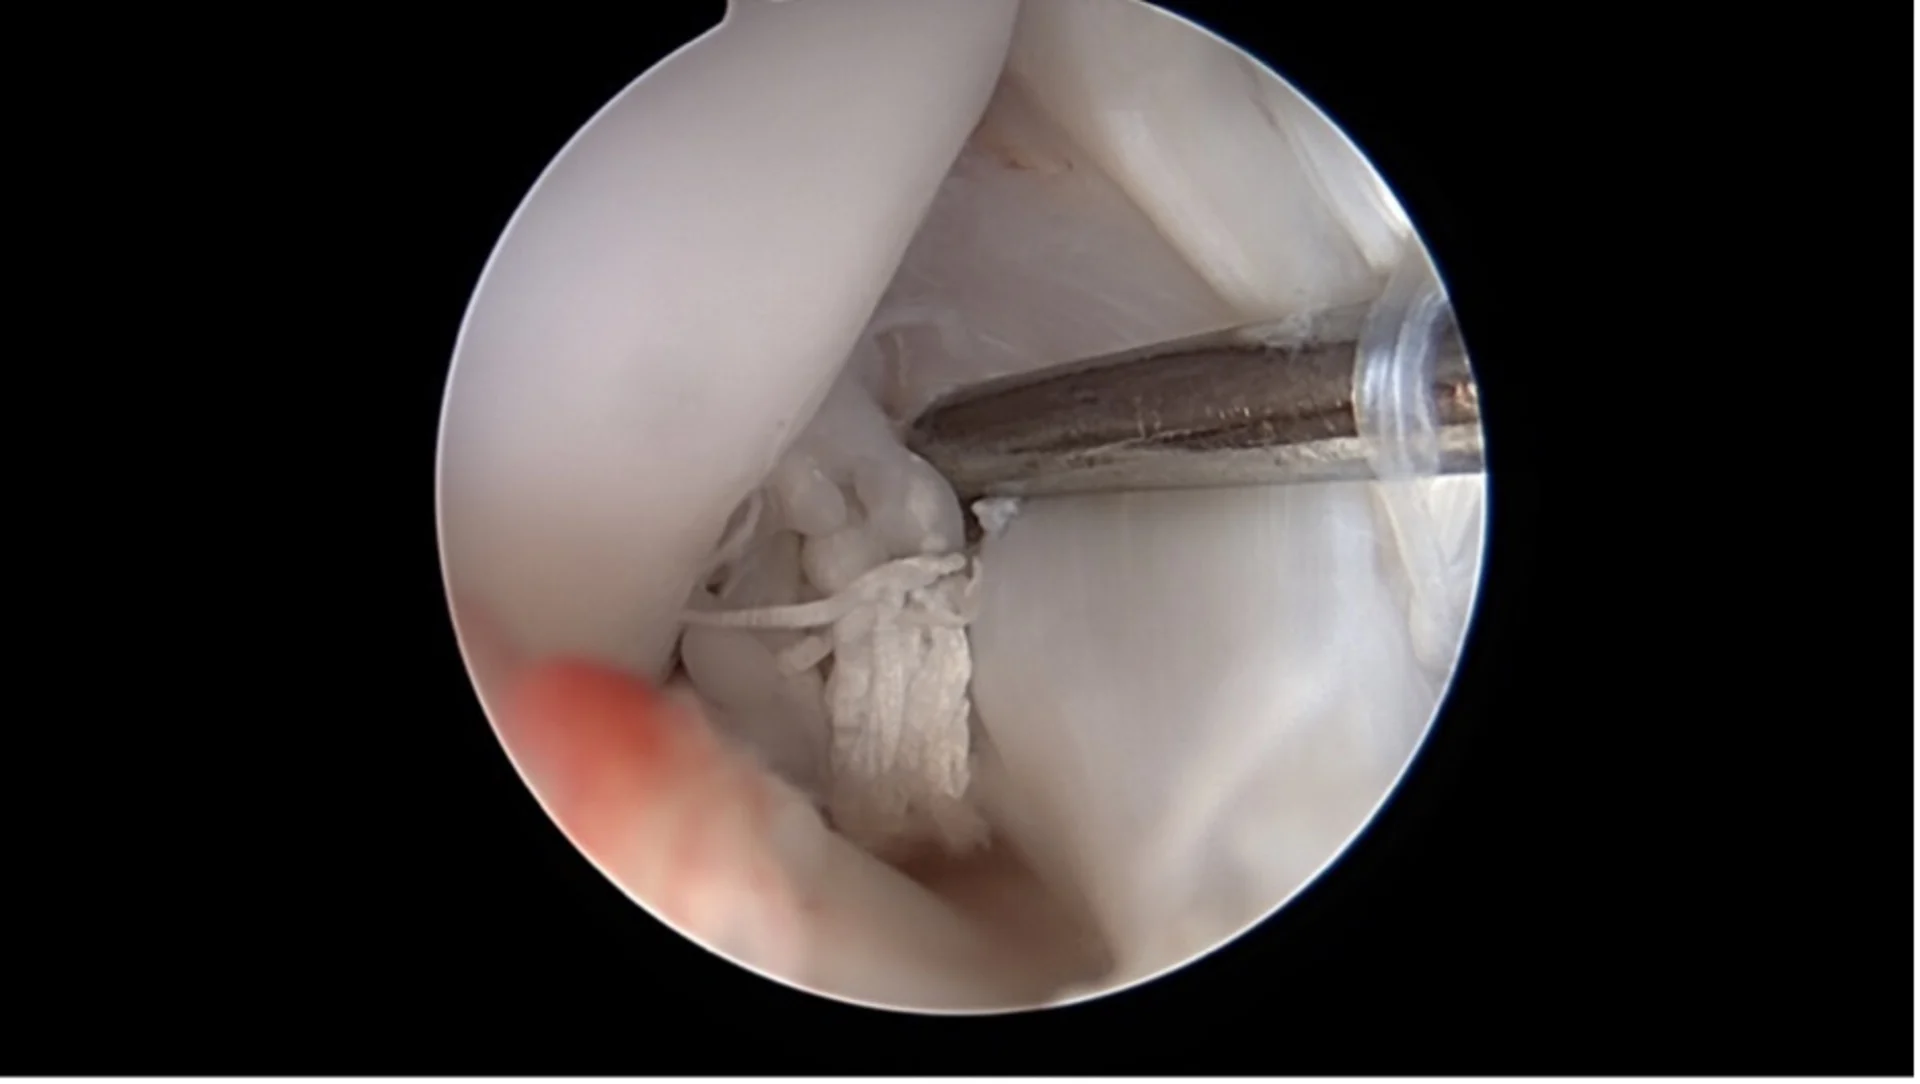

Ein beginnender Kreuzbandriss versteckt sich unter dem auf dem ersten Blick unauffälligen restlichen Kreuzband

Ein kompletter Kreuzbandriss

Arthroskopie: Diese Technik ermöglicht eine direkte Sicht auf das Gelenkinnere mit Hilfe einer kleinen Kamera. Über nur wenige Millimeter grosse Hautöffnungen lassen sich Veränderungen am Kreuzband sowie begleitende Schäden wie Meniskusrisse erkennen und in vielen Fällen auch direkt behandeln.

Korbhenkel-artiger Meniskus Riss

Nanoskopie: Noch feiner als die Arthroskopie bietet die Nanoskopie die Möglichkeit, mit besonders kleinen Instrumenten und hochauflösender Bildtechnik im Gelenk zu arbeiten. Das Verfahren ist besonders geeignet für kleinere Hunde. Beide Methoden sind minimalinvasiv, verursachen wenig Gewebetrauma und ermöglichen eine schnellere Erholung.